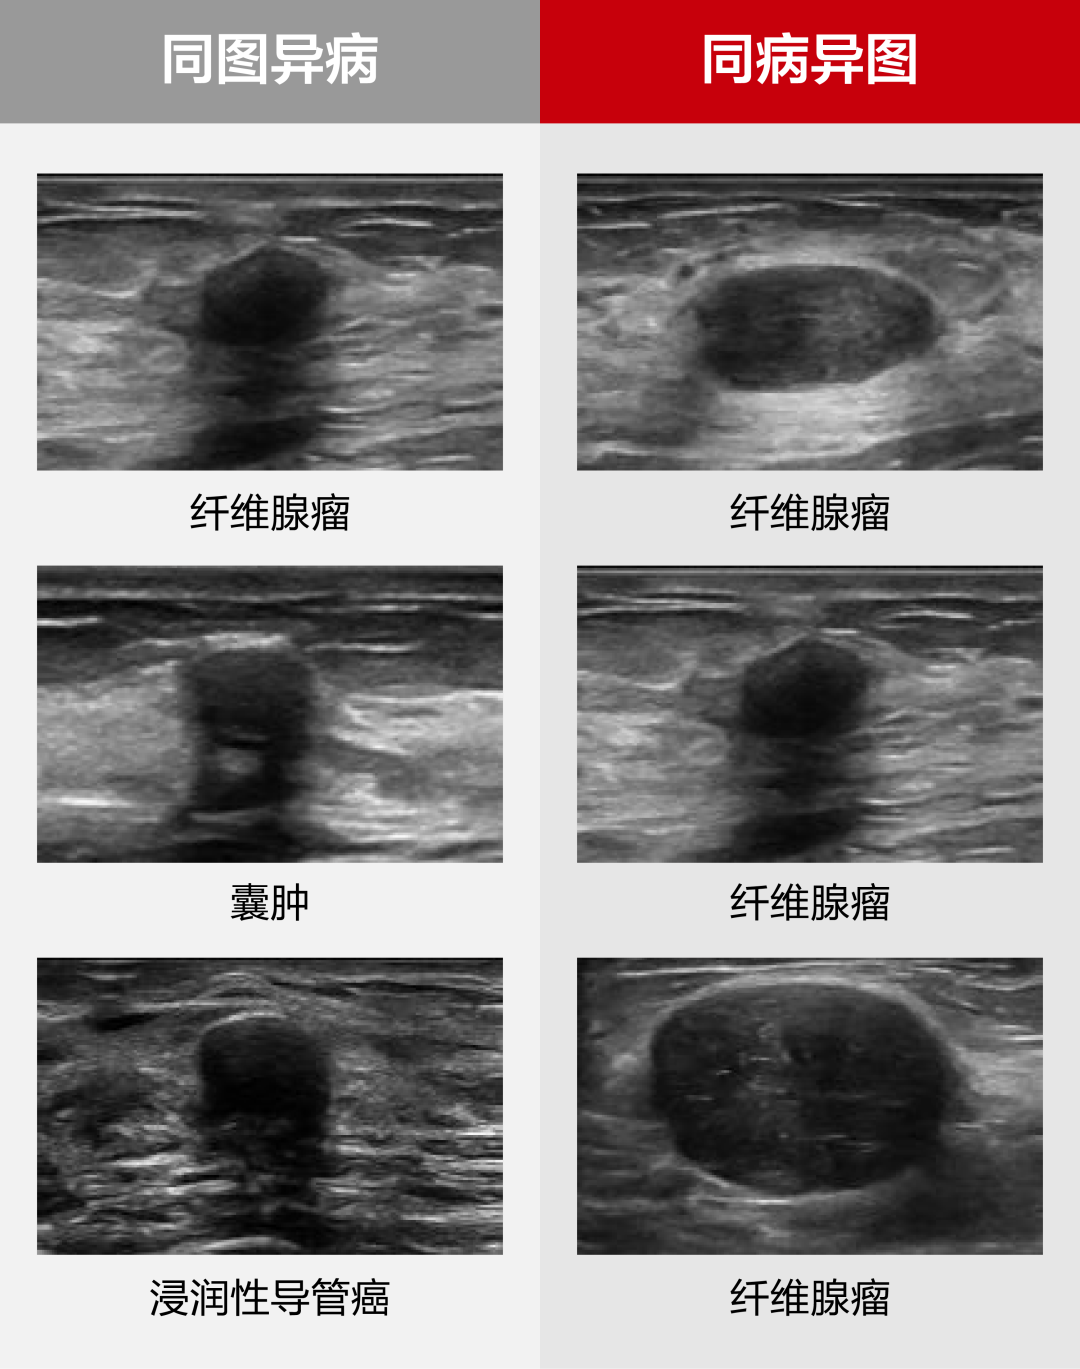

然而,单切面二维图像的局限性、病例表征的非特异性、恶性肿瘤的隐匿表征,以及超声经验积累周期长等问题,成为全球超声医学发展亟待解决的难点。乳腺病灶的精准诊断评估在临床上仍面临巨大挑战,尤其困扰经验较缺乏的年轻超声医生。

为了应对这一挑战,迈瑞以《乳腺疾病超声检查质量控制专家共识(2019版)》为基准,以覆盖实际临床场景的图像与专家组诊断结果,作为训练数据及金标准,通过创新的深度学习算法,将临床知识与高年资医生对图像判读的经验融入辅助诊断模型中,即使面对复杂病变,软件也可以给出高效精准的临床分类诊断。